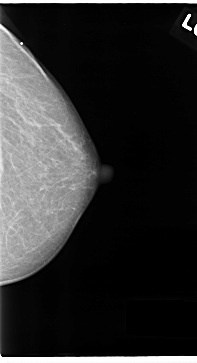

C_0122_1.RIGHT_MLO

RIGHT_MLO LINES 4696 PIXELS_PER_LINE 2568 BITS_PER_PIXEL 12 RESOLUTION 50 NON_OVERLAY